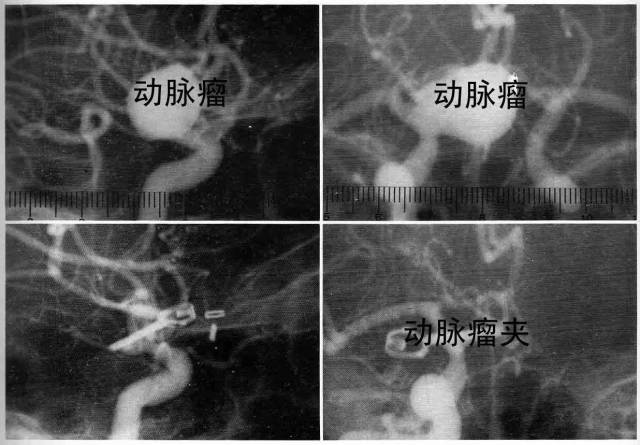

影像学表现–DSA:

DSA是诊断颅内动脉瘤最准确的方法,可清晰显示动脉瘤部位、大小、数量、形状。为了发现预料之外的动脉瘤,血管造影应包括所有部位的脑内血管。

造影应在出血后立刻进行,否则,出血2~3天后即发生血管痉挛,持续大约1周,此时造影,容易出现假阴性。

1、直接手术,其中瘤颈夹闭是最好的方法。